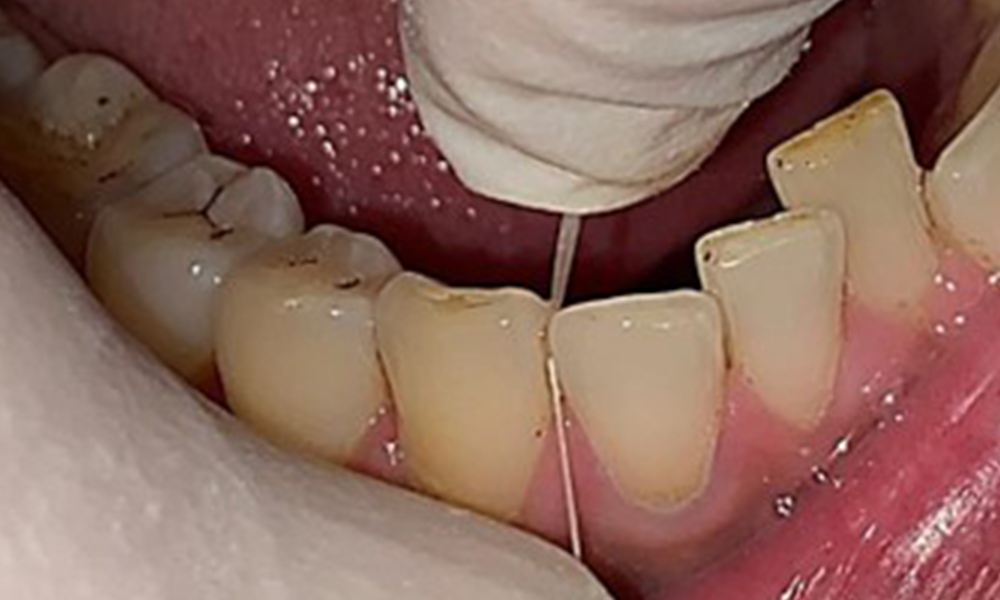

The patient has full dentition with a total of 28 teeth. There were noteworthy erosions and attritions. (Fig. 4, Fig. 5). Due to bruxism, the patient has been wearing a splint with an adjusted bite block at night for many years. The erosions were caused by long-term consumption of isotonic beverages. No periodontal bone loss or active caries were observed.

Full complement of adult teeth with no caries or radiologically recognizable bone loss was observed (Fig. 6). Radiological enamel and cusp loss were particularly evident on 36 and 37.

Instruction and motivation are important components of these appointments. Good home-based intraoral hygiene behaviour and understanding are important for patients. Plaque accumulation is particularly evident in the cervical regions (Fig. 8).

These must be discussed with the patient, and improvements to the teeth-brushing technique must be practised. A soft toothbrush attachment is recommended for home-based intraoral hygiene due to the presence of erosions and attritions.